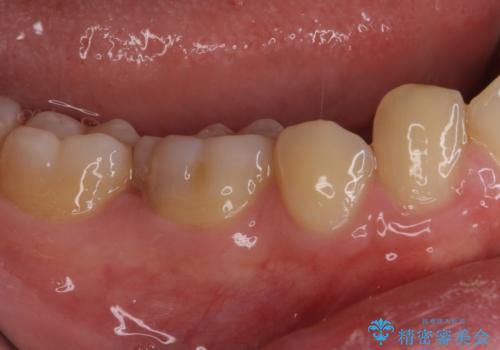

- 下顎左右奥歯に虫歯で痛みを感じるとのことで来院された患者様です。

むし歯が大きく、神経を取り除く可能性があることを理解いただいた上で虫歯を取り除き、その後はオールセラミッククラウンにて補綴することとしました。